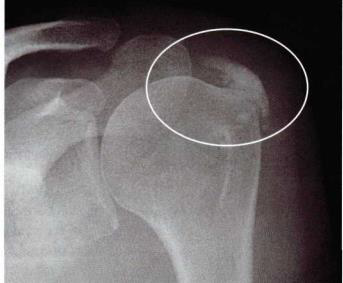

Pacientes com luxação recidivante do ombro podem apresentar sinais radiográficos característicos: o sinal de se apresenta como uma erosão óssea na região posterior da cabeça do úmero, e o sinal de é caracterizado por uma lesão óssea ou no labrum da glenoide anterior e inferiormente.

Assinale a alternativa que preenche, correta e respectivamente, a lacuna do texto:

Analise a imagem, abaixo:

Observa-se acentuadas calcificações na topografia da inserção do tendão: